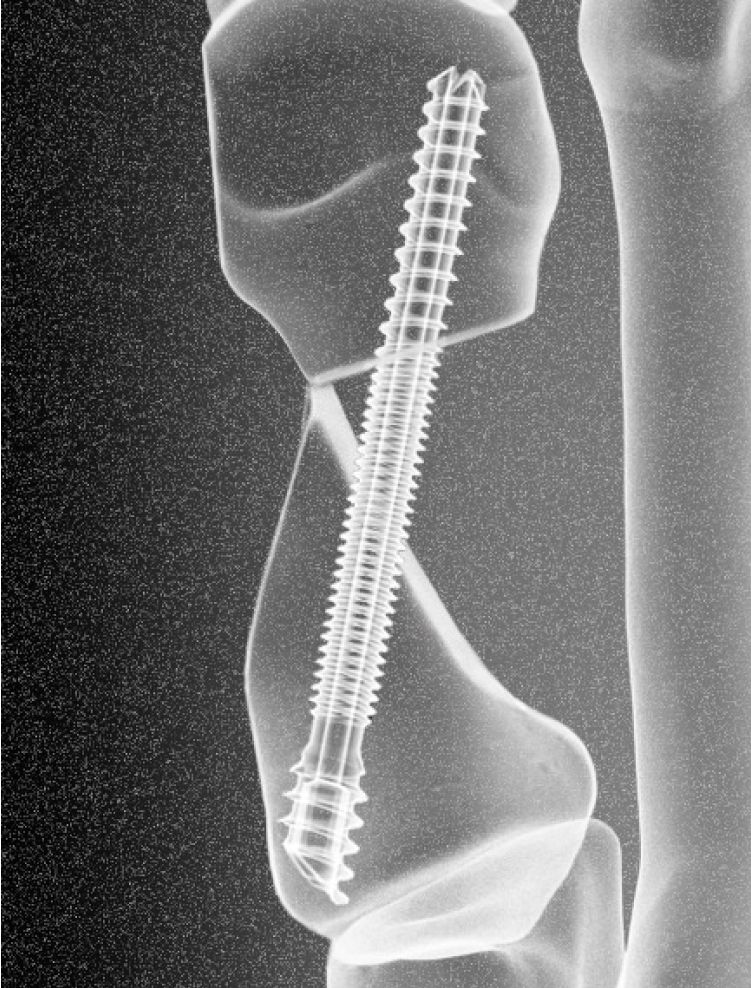

- next generation mibs screw

The Revcon™ Minimally Invasive Screw System heralds a groundbreaking advancement, offering the exclusive No-Fusion Bunion Solution™ with patented screws tailored for minimally invasive bunion treatment. Designed by surgeons, for surgeons, both the Revcon™ Neutra v1.0 and our next advancement – the Revcon™ Anchor v2.0 – feature a neutral, non-compressive screw pitch, specially engineered to stabilize bone segments, fostering bony healing and regeneration, an essential aspect of MIBS.

“Our Revcon™ Anchor screw is an unparalleled product differentiator, representing a revolutionary solution for bunions,” says Dr. Neal Blitz, DPM, Founder and CEO of Voom. “The Revcon™ Anchor screw stands as the only dual-zone pitched screw explicitly designed for capturing different bone densities in bunion repair, using Voom’s proprietary Transveron™ bone cutting and realignment techniques.

Both screws are part of the Revcon™ Minimally Invasive Screw System, and have received FDA clearance for various foot indications and osteotomies, particularly for hallux valgus (bunion) treatment.